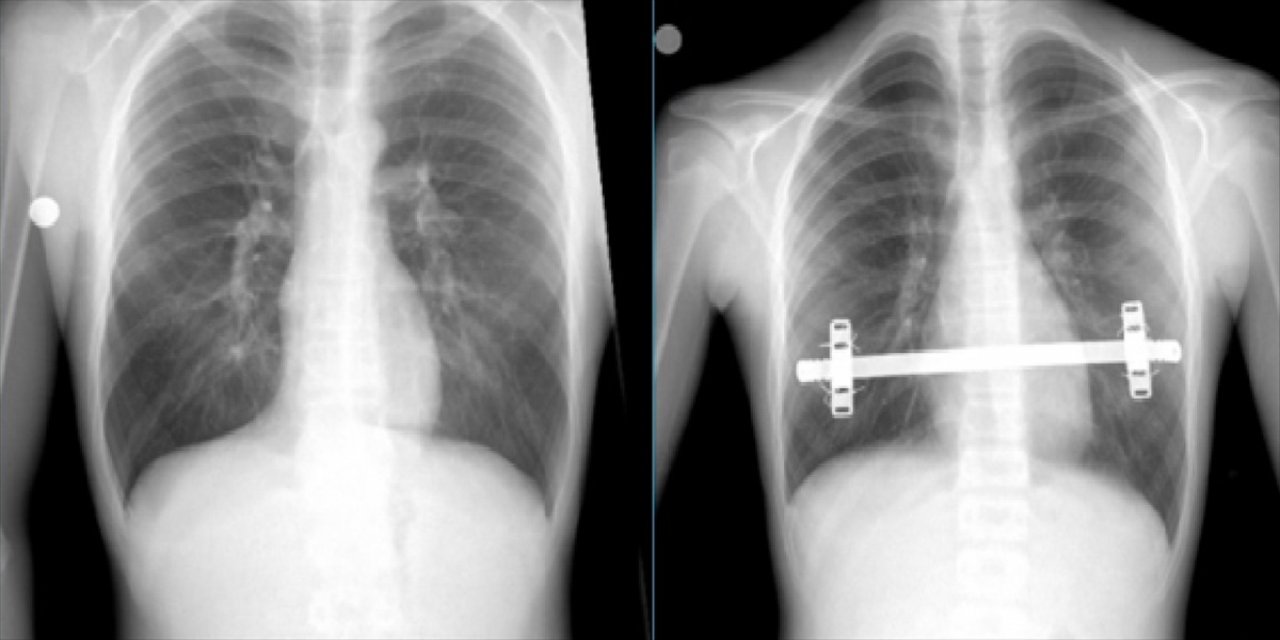

TRABZON (AA) - Trabzon'da, halk arasında "kunduracı göğsü" olarak bilinen Pektus Ekscavatum hastalığı ile mücadele eden Hamza Suiçmez, 2 saat süren ameliyatın ardından sağlığına kavuştu.

Karadeniz Teknik Üniversitesi (KTÜ) Farabi Hastanesinden yapılan açıklamaya göre, erken yorulma, çarpıntı, göğüs duvarında şekil bozukluğu ve şekil bozukluğu kaynaklı psikolojik olarak kendini sosyal çevresinden kısıtlama şikayetleri bulunan 26 yaşındaki Hamza Suiçmez, hastaneye müracaat etti.

Suiçmez'e, yapılan tetkikler neticesinde halk arasında "kunduracı göğsü" olarak da bilinen Pektus Ekscavatum hastalığı tanısı konuldu.

Erken yorulma ve çarpıntı şikayetlerinin, içeri doğru basık olan iman tahtasının kalp üzerine baskı yapmasından kaynaklandığı anlaşılan hasta, KTÜ Farabi Hastanesi Başhekimi ve Göğüs Cerrahisi Anabilim Dalı Başkanı Prof. Dr. Celal Tekinbaş ve ekibi tarafından ameliyat edildi.

"Kapalı kunduracı göğsü ameliyatı (NUSS)" uygulanmasının ardından sağlığına kavuşan Suiçmez, şikayetlerinin artık olmadığını ve en önemlisi de kendisini daha özgüvenli ve sosyal hissettiğini belirtti.